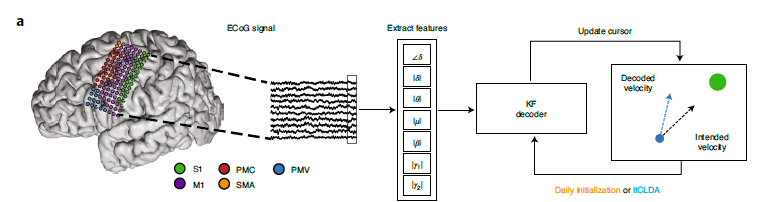

a,游标控制管道。参与者大脑MRI上覆盖的ECoG电极(按解剖区域着色)的图示。在速度卡尔曼滤波(KF)解码器中,将ECoG信号连续流、滤波并合并到神经特征中。解码器权重是通过闭环解码器自适应过程(CLDA)学习的。S1,初级体感皮层;M1,初级运动皮层;PMC,运动前皮层;PMV,腹前运动皮层;和SMA,辅助运动区域。